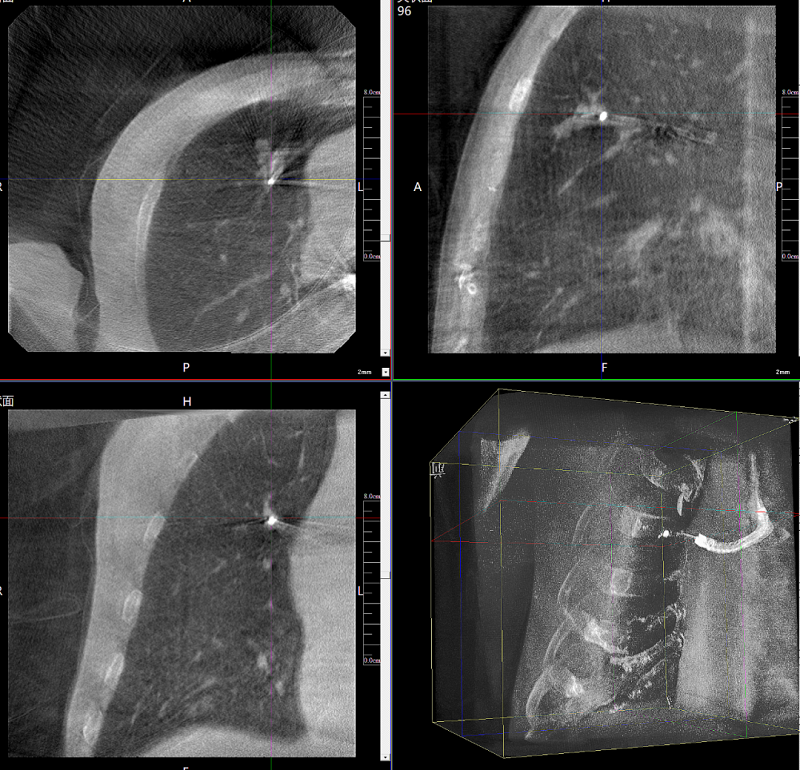

病例3:超聲支氣管鏡下肺活檢(80歲)

三維C形臂還可以創新性地應用在呼吸介入領域。例如,在經皮穿刺或經支氣管鏡肺結節活檢、定位、消融等場景中,用于確認工具是否到達病灶、消融范圍是否完全覆蓋病灶等。

二維影像無法準確判斷工具是否到達病灶

三維各切面影像都顯示工具達到病灶內